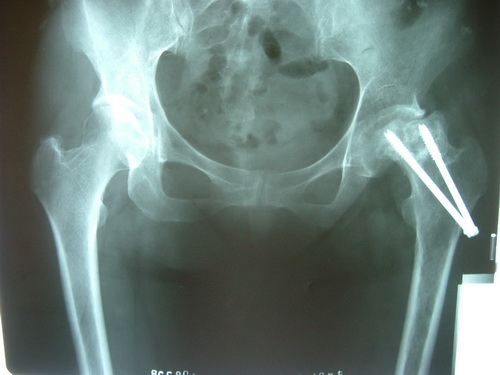

二院骨三科2011首先在焦作市开展的股骨头坏死微创减压植骨术,